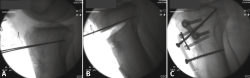

Figura 11. Escopia intraoperatoria de una osteotomía de deflexión. A: colocación de aguja guía paralela a la pendiente tibial; B: extracción de la cuña anterior una vez realizada la osteotomía preservando un puente óseo posterior; C: fijación de la osteotomía de cierre anterior con 2 placas de epifisiodesis y de la tuberosidad tibial con 2 tornillos corticales.

Se utiliza una incisión longitudinal anterior centrada o levemente medial a la tuberosidad tibial anterior (TTA). Primero se realiza una osteotomía de la TTA con un bloque óseo de 6 cm que se rebate hacia lateral permitiendo el acceso libre a la parte proximal de la tibia. La osteotomía de deflexión se realiza de acuerdo con el cálculo preoperatorio. Bajo el control fluoroscópico, se insertan 1 o 2 agujas guía desde la cortical anterior a la posterior de la tibia para marcar el sitio de la osteotomía, comenzando aproximadamente 3-4 cm distal a la interlínea articular, en dirección de la inserción del ligamento cruzado posterior (LCP) (Figura 11A). Mantener un puente óseo posterior intacto es fundamental para proteger las estructuras poplíteas y limitar el riesgo de desplazamiento secundario o pseudoartrosis (Figura 11B). El objetivo es obtener una PTP de entre 0 y 10° según la gravedad de la deformidad y la inestabilidad de la rodilla. La osteotomía de cierre anterior se fija con 2 grapas o 2 placas de epifisiodesis de tipo 8 colocadas en la parte medial y lateral con respecto a la TTA. La tuberosidad se vuelve a reposicionar desplazándola distalmente con una cantidad igual al grosor del fragmento óseo eliminado, para evitar el cambio postoperatorio de la altura patelar, y se fija con 2 tornillos corticales anteroposteriores: uno superior y otro inferior a la osteotomía (Figura 11C).